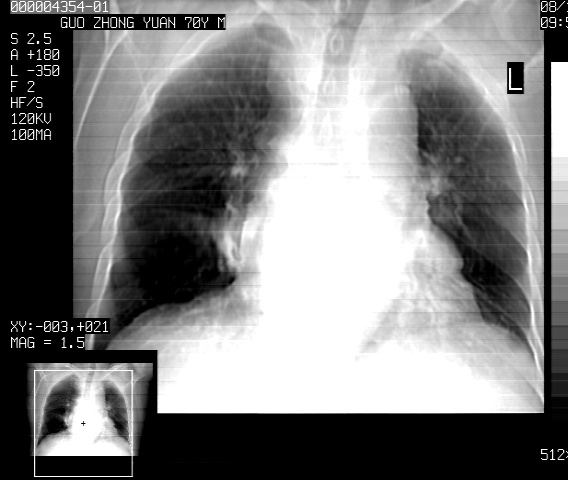

以下是引用sdzyy在2008-12-1 11:49:00的发言:[br]图像不全,请上传,右下肺炎症可能性大,占位待排.

以下是引用zjzjr在2008-12-1 14:53:00的发言:[br]图像不全,请上传,右下肺炎症可能性大,占位待排.心影增大,建议进一步检查.